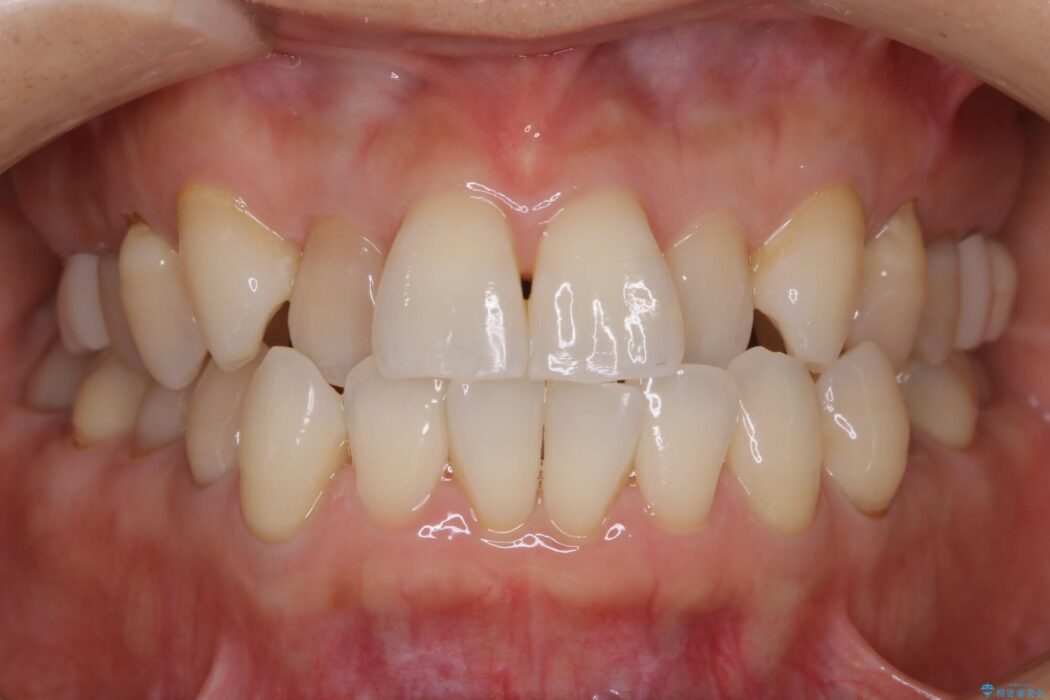

前歯のガタつき、噛み合わせの不調を改善したいとご来院されました。

全体的に歯列が狭窄しており、本来外側に覆いかぶさっている上の前歯が内側に入り込んでいました。

気になっていたガタつきも改善され、患者様にはご満足いただけました。